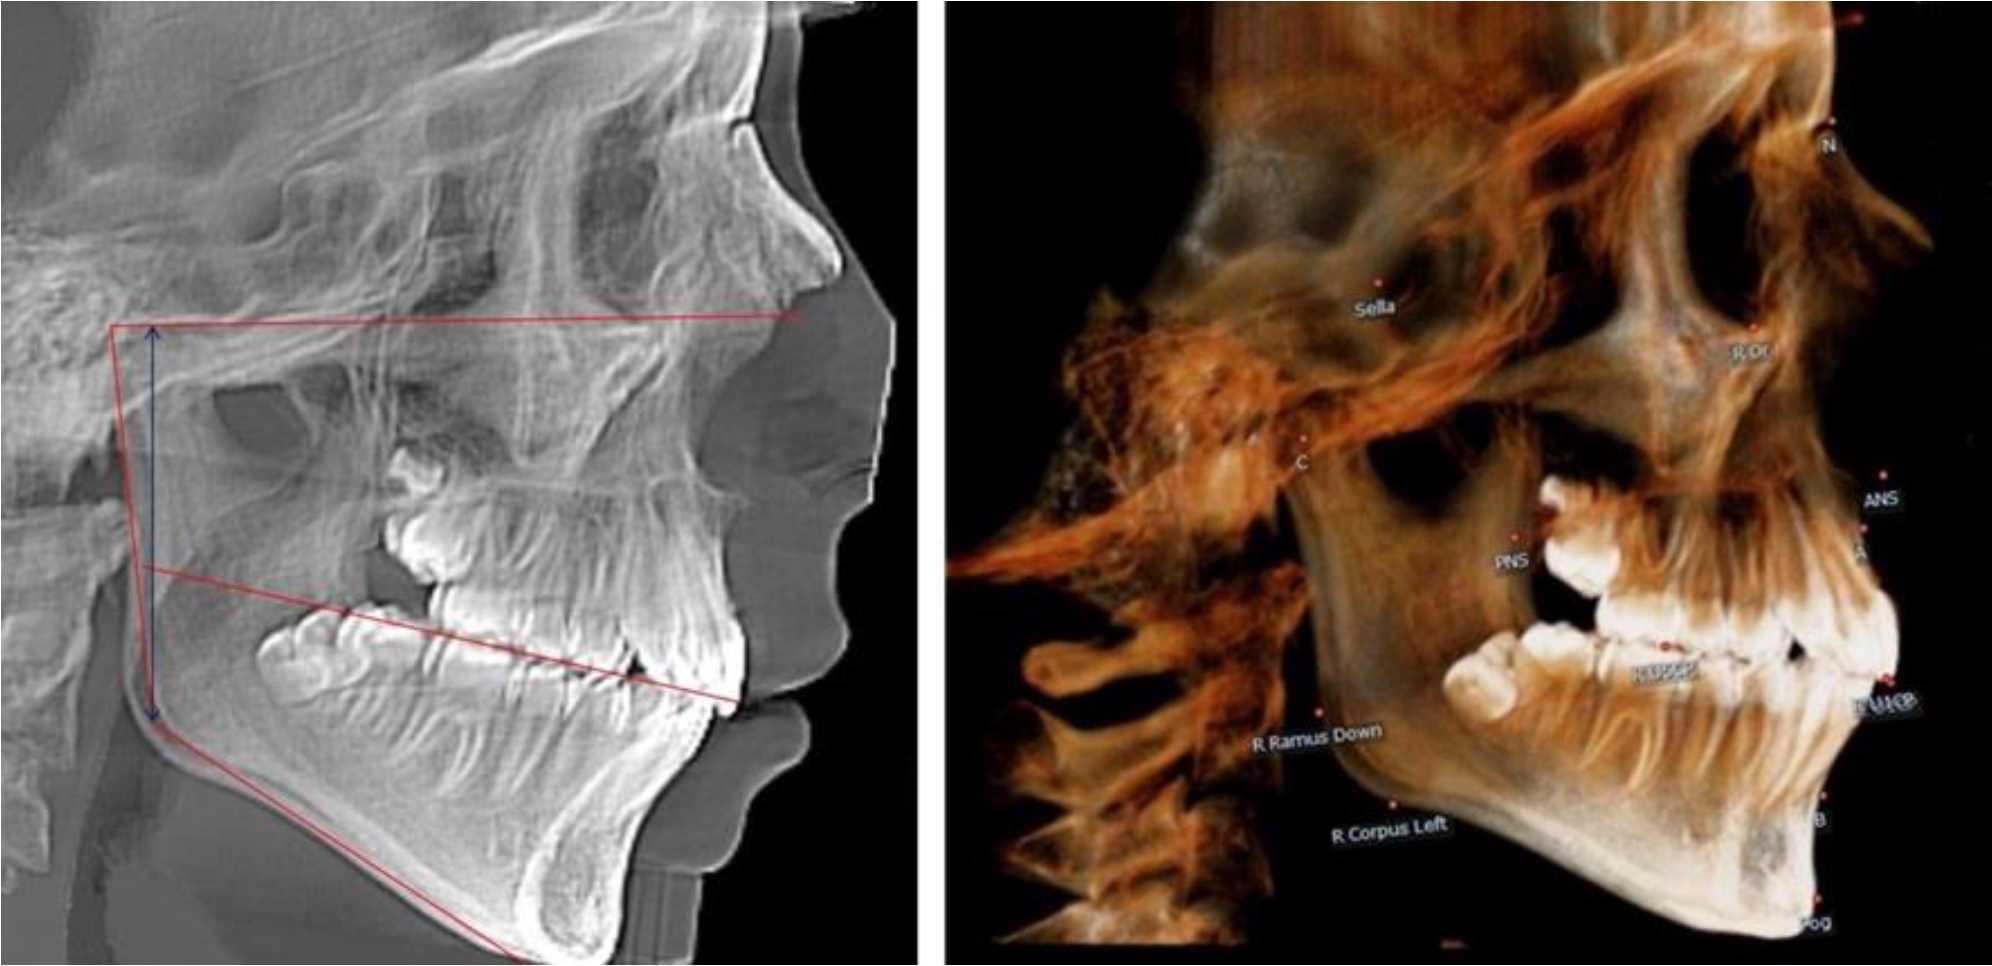

В 1-й группе были проанализированы 7 телерентгенограмм и 7 ортопантомограмм, что составило (6,60 ± 2,41) % от числа изученных рентгенограмм. На всех парах рентгенограмм угол нижней челюсти, измеренный на телерентгенограмме, соответствовал углу, полученному при построении угла на ортопантомограмме. Окклюзионная линия практически однотипно делила ветвь на два отдела (рис. 1).

Рис. 1. ТРГ и ОПТГ пациента 1-й группы

Рис. 2. ТРГ и ОПТГ пациента после прорезывания первых постоянных моляров

В 5-й группе были проанализированы 14 комплектов рентгенограмм, что составило (13,21 ± 3,29) % от общего числа. На всех рентгенограммах отмечен очередной этап подъема высоты прикуса, обусловленный прорезыванием вторых постоянных моляров. Окклюзионная линия делила ветвь на два отдела (рис. 5).

Рис. 5. ТРГ и ОПТГ пациента после смены молочных зубов и прорезывания вторых постоянных моляров